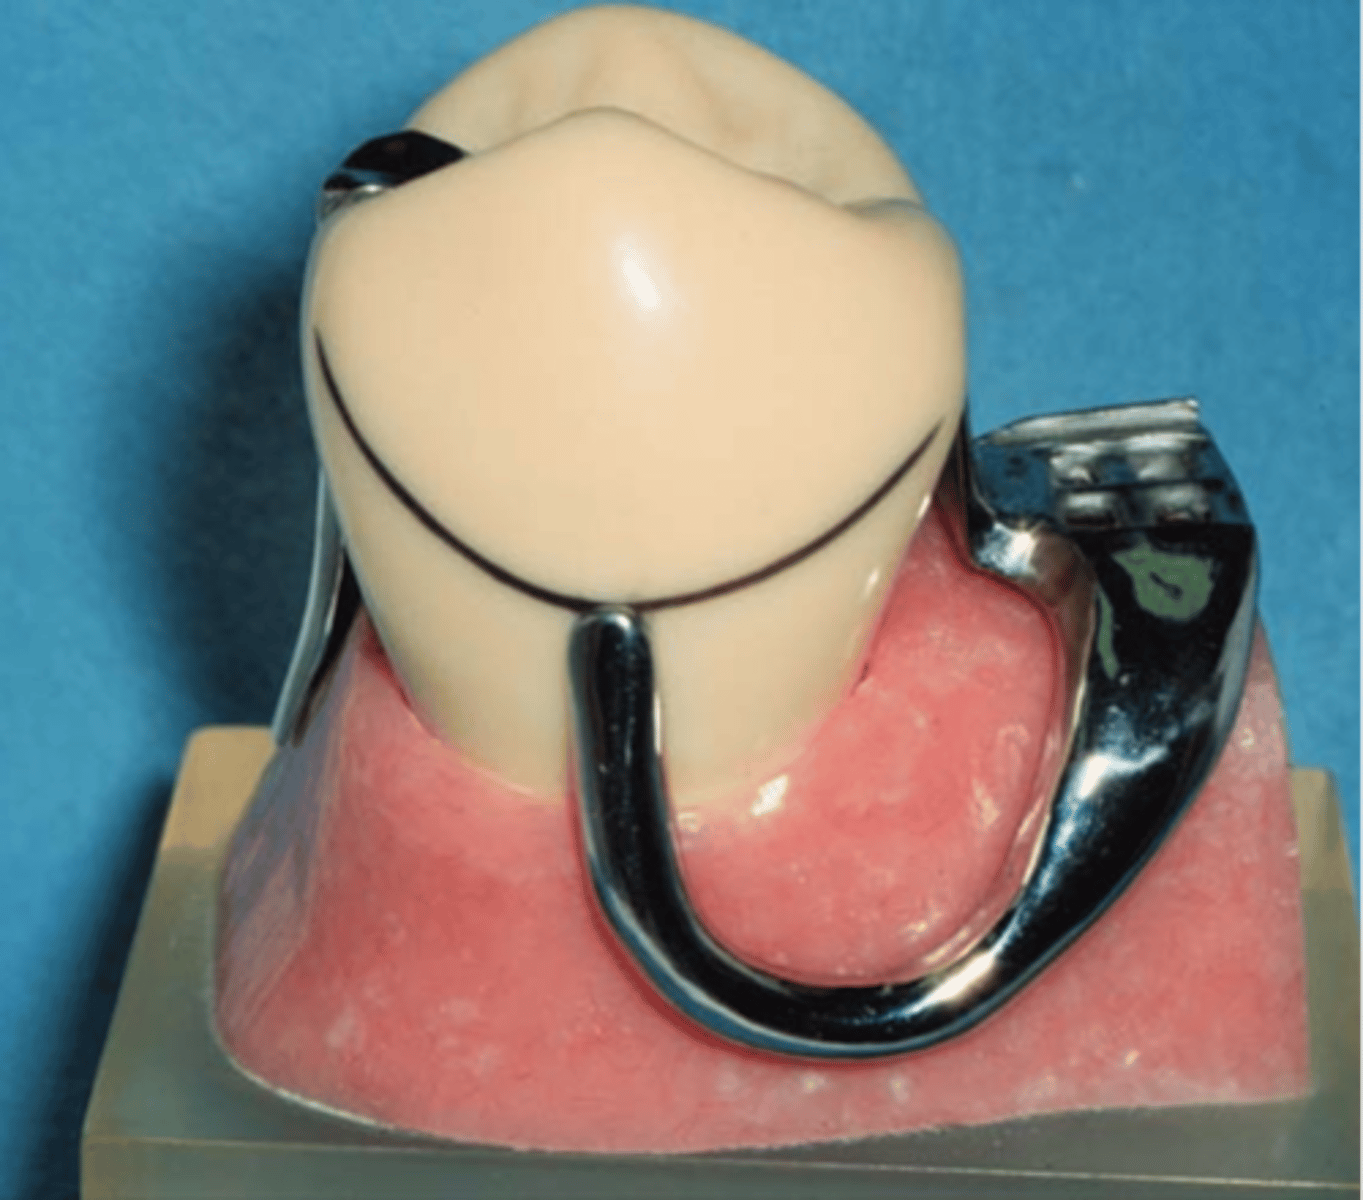

Infrabulge (Bar) Clasps

clasp

• Retentive tip in gingival 1/3 of tooth

• More esthetic

• Less contact (Hygiene)

• Cast infrabulge clasps: Stress releasing design compensates for the difference in movement between teeth and mucosa – good for adjacent to distal extension areas, if an abutment is periodontally involved, if extensive edentulous space is present

---RPI clasp assembly (MESIAL rest, proximal plate, I bar)

---Other options: T bar, half T bar, etc

MESIAL rest, proximal plate, I bar

RPI stands for

insufficient vestibular depth, large soft tissue undercuts (a)

I Bar contraindications